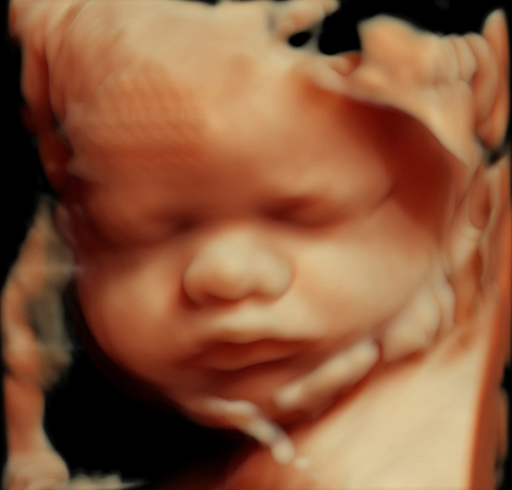

产科_胎儿面部_胎儿颜面三维成像:正常

产科_胎儿面部_胎儿颜面三维成像:唇裂